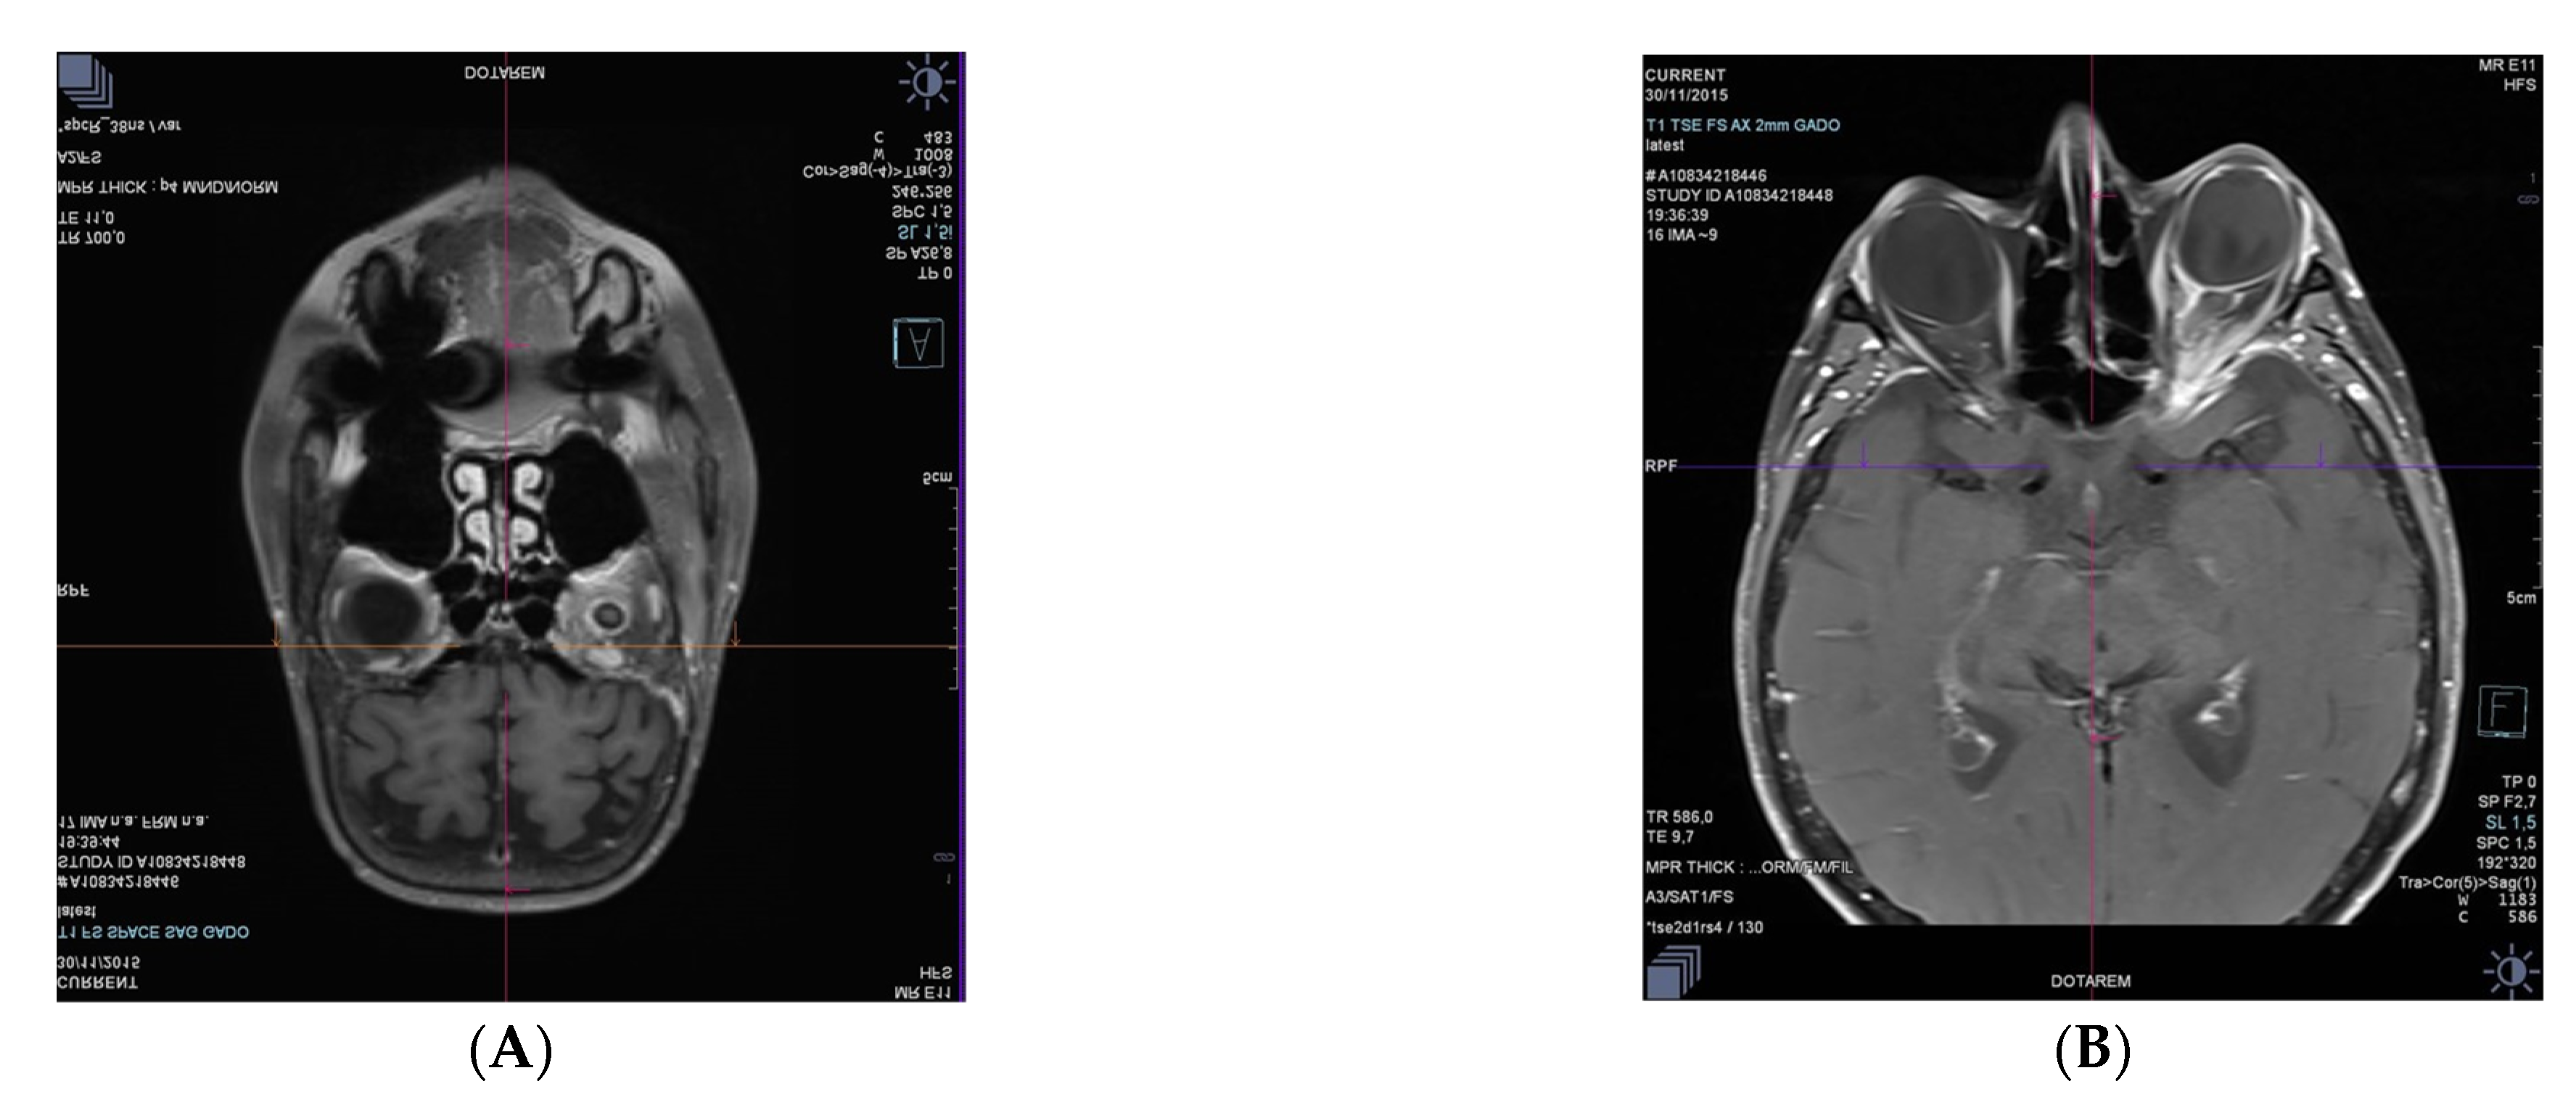

3.1.3. Case 3. Orbital Relapses in the Case of Systemic DLBCL, despite Auto and Allograft Transplant of Hematopoietic Stem Cells

3.1.4. Case 4. First Vitreous Relapse in the Case of Systemic DLBCL, despite CAR T-cell Therapy with Axicabtagene Ciloleucel. Second Retinal Relapse in the Form of a Retinitis after Pembrolizumab Infusions, Intravitreal Methotrexate, and Intrathecal Methotrexate